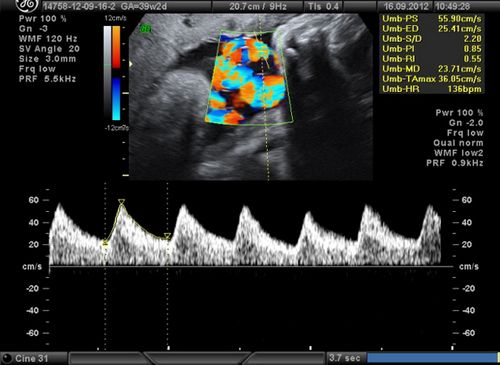

Допплерометрия

Це питання слід розглянути окремо. Допплерометрия є дослідження руху крові в серці та судинах.

На ранній стадії вагітності вимірюванню підлягає кровотік в маткових артеріях, так як певні показники можуть свідчити про затримку розвитку плода.

Крім того, допплерометрия допомагає в тих випадках, коли спостерігаються вагітні жінки, які страждають судинними порушеннями і цукровим діабетом.

На 18-20 тижні досліджується серце плоду на предмет наявності вад серця. З наближенням 32 тижня можливе застосування допплерометрії для оцінки загального стану плода. Також корисно вивчення артерій пуповини, що дозволяє встановити, чи є маловагі плід здоровим чи ні.

Відмінною рисою доплерометричного методу є його неінвазивний і оперативність: з його допомогою можна швидко встановити, наскільки порушено функціональний стан плода при наявності патологій.